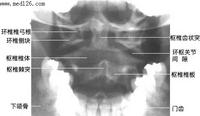

标题: x2554:枢椎棘突密度减低区,请会诊! [打印本页]

女,45岁,近来感颈部疼痛,头晕,夜不能寐,按之枢椎棘突,感有硬结感,疼痛,骨科怀疑骨囊肿,拟手术,请大家帮忙看一下,是否是正常的?

楼主所指的枢椎棘突密度减低区属正常表现,你可能多拿几个颈椎侧位片看看。

下面是我刚从网上下载的几张颈椎图片。